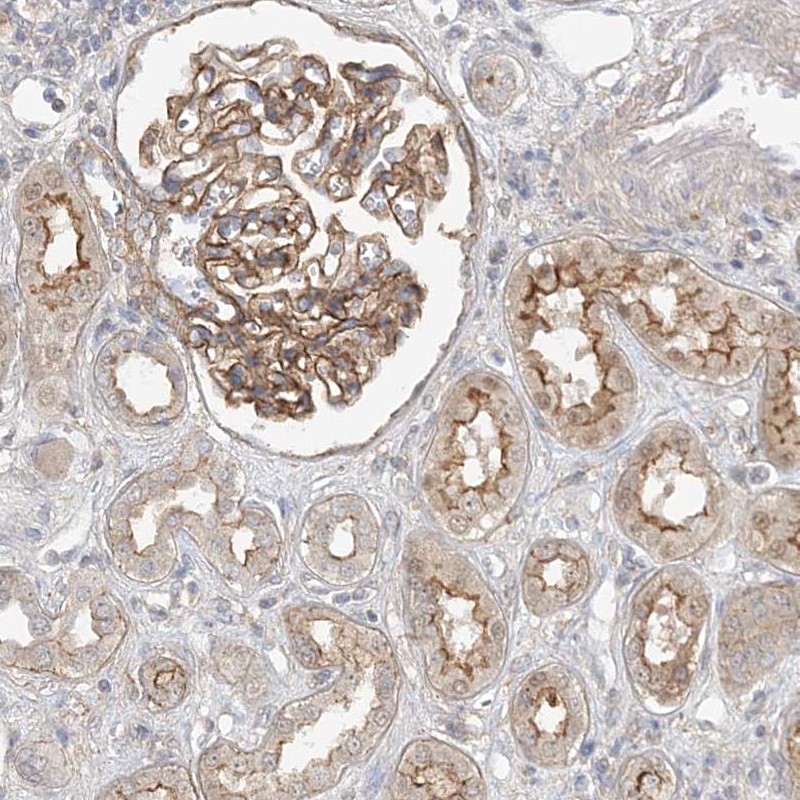

Immunohistochemical staining of human kidney shows moderate membranous positivity in cells in tubules and in glomeruli.